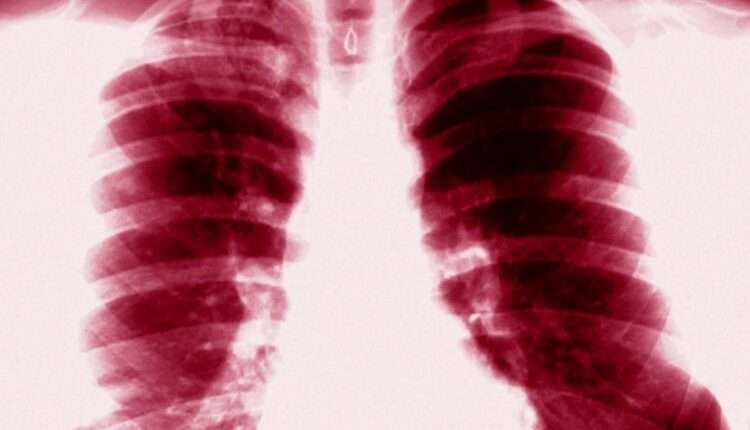

د طالبانو د عامې روغتیا وزارت د پلان او پالیسۍ مرستیال ډاکټر غیاثي د نري رنځ د تېر کال ارقامو په اړه وویل: «په تېر کال کې شاوخوا ۷۶ زره قضیي ثبت شوي او ۴۸۰۰ له درملو سره مقاوم قضیې رامنځته شوي. ددغو ارقامو له ډلې ۵۲ زره یې د توبرکلوز د کنټرول پروګرام لخوا کشف او تر درملنې لاندې نیول شوي دي. هر کال شاوخوا ۱۰ تر ۱۲ زره کسان خپل ژوند له لاسه ورکوي.»

په ۲۰۲۱م کال کې چې د طالبانو د واکمنۍ لومړی کال وو، د طالبانو روغتیا وزارت د نري رنځ د شاوخوا ۵۲ زره پېښو د ثبتيدو اعلان کړی وو. دغه وزارت ویلي ول چې د نري رنځ له امله ۱۱ زره افغانانو خپل ژوند له لاسه ورکړی دی. د روغتیا په برخه کې د طالبانو مسؤولان وایي چې په ټولو ولایتونو کې د نري رنځ یا توبرکلوز ناروغۍ د درملنې ۸۷۷ مرکزونه شتون لري چې د نړیوالو مؤسسو په مرسته په وړیا توګه خدمات وړاندې کوي.

دوی له نړیوالو روغتیایي سازمانونو څخه غواړي چې د نري رنځ ناروغۍ د مبارزې په برخه کې خپلې همکارۍ زیاتې کړي. روغتیا پالان بیا وایي چې که چېرې د نري رنځ ناروغۍ په وخت درملنه ونه شي، د اخته کس د مرګ لامل کېږي.